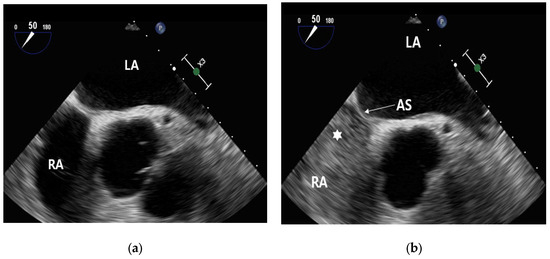

2.2.1. Cardiac Testing

2.2.3. Contrast-Enhanced Transesophageal Echocardiography